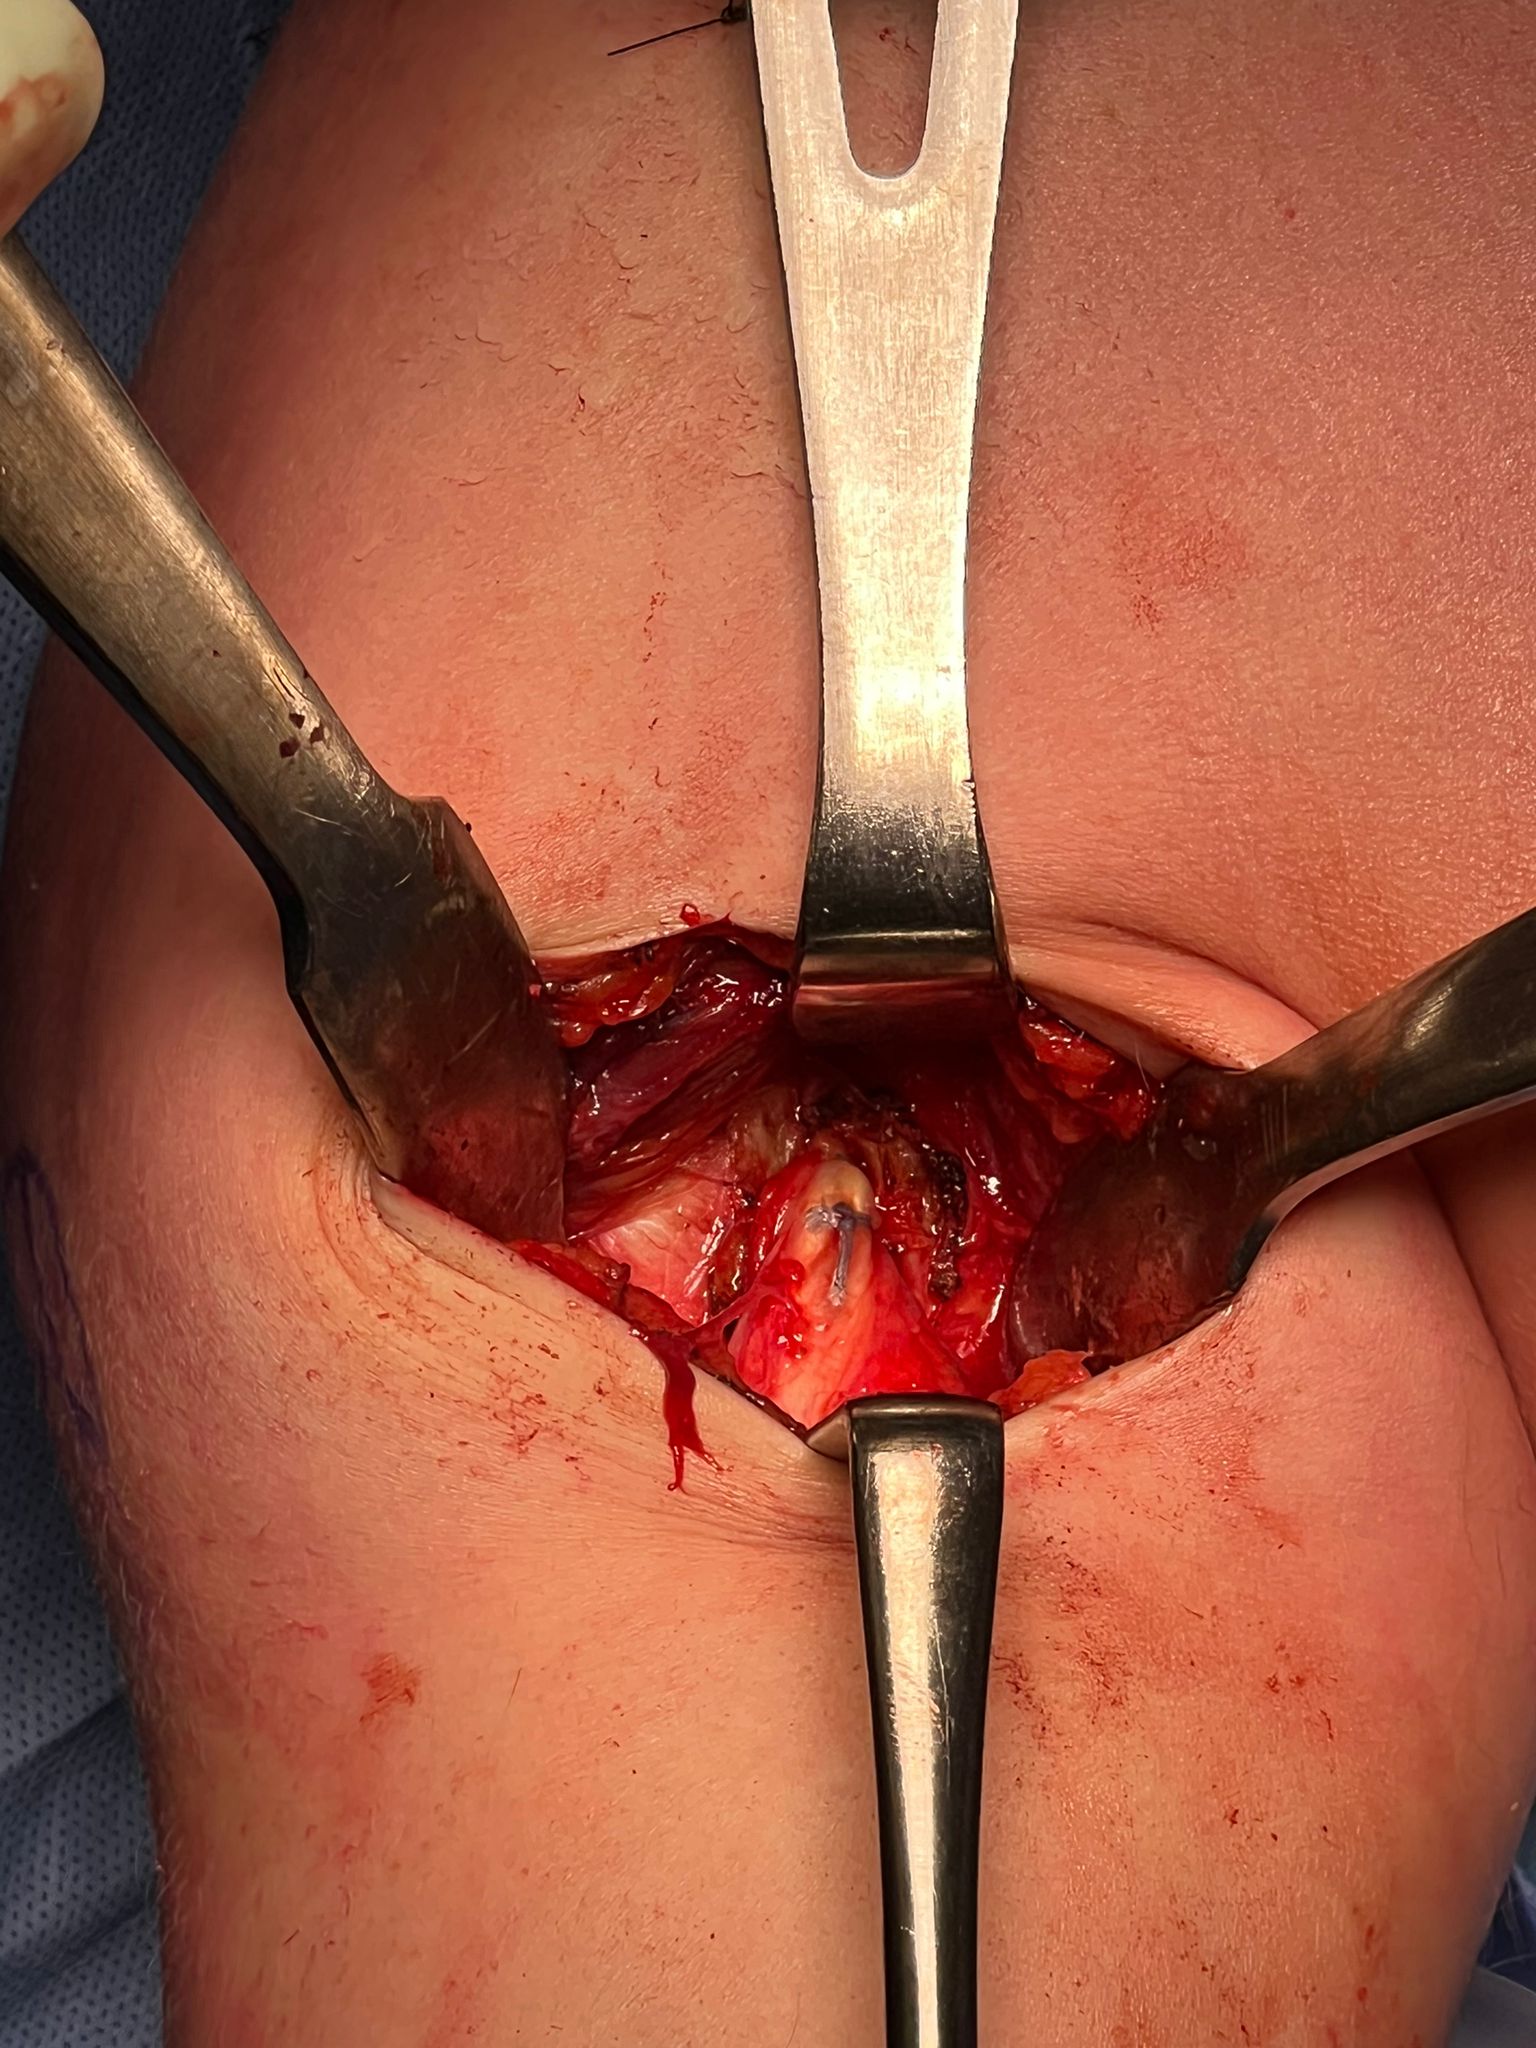

Open subpectoral biceps tenodesis

Technique

Beachchair

- arthroscopic biceps tendon release

- open approach to biceps

- incision centered on humerus below pectoralis tendon

- retract deltoid laterally / elevate pectoralis tendon / conjoint tendon medially

- find biceps tendon / shorten to 2cm of tendon / suture

- anchor biceps tendon

Bicortical open subpectoral biceps tenodesis using Arthrex Biceps Button